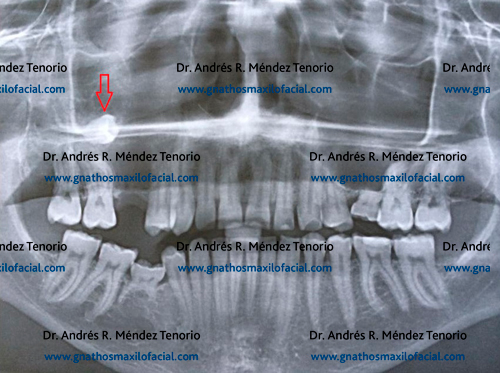

| Radiografia panorámica mostrando 3os molares. Del lado izquierdo (flecha) ante la ausencia del inferior, el 3er molar superior se ha salido de su plano y lastima la mucosa de la mandíbula |